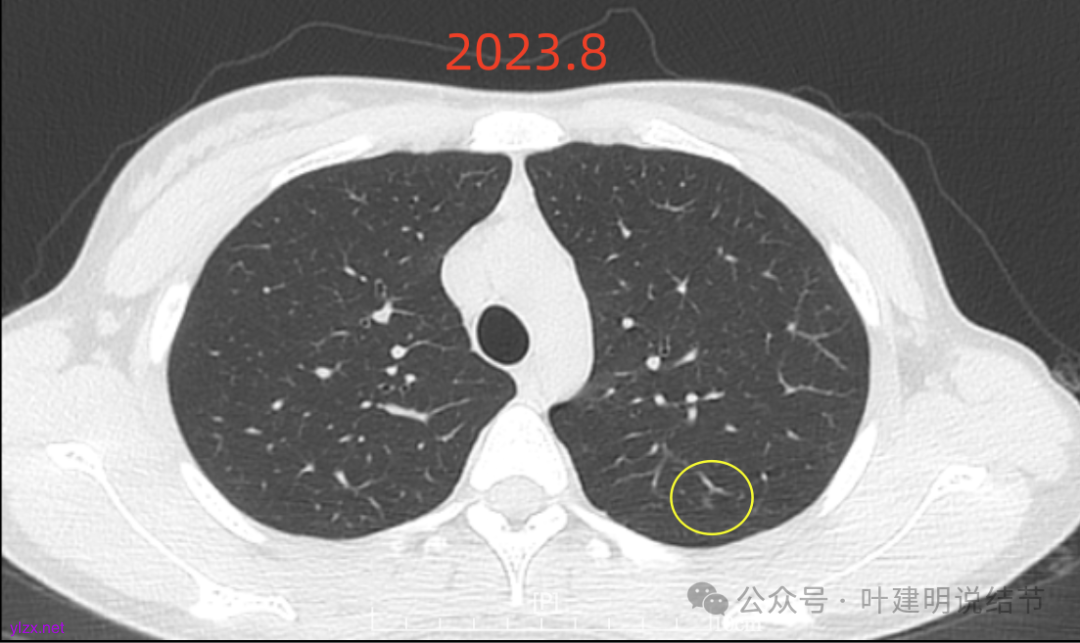

先来看2023年8月的:

病灶6:右下叶脊柱旁囊腔型病灶,整体轮廓与边界清,没有明显实性成分,考虑原位癌或微浸润性腺癌可能性大。

各病灶均无明显吸收好转,但显然也说不上有明显进展。所以基本上要考虑是肿瘤范畴的(包括肺泡上皮不典型增生或肺泡上皮增生)。但危险性显然不算高,至少近2年了没有什么进展,即使病灶6最厉害的也是纯磨密度伴空腔。